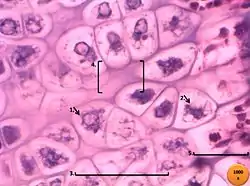

Los condrocitos son las células encargadas de mantener la homeostasis fisiológica del cartílago articular, sintetizando colágenos, proteoglicanos y proteinasas que forman parte de la matriz extracelular. Sin embargo, alteraciones en el proceso de diferenciación de los condrocitos produce una matriz extracelular de menor resistencia y elasticidad, además de un desbalance entre la síntesis y degradación de la misma. Esto se debe a la hipertrofia de los condrocitos, cuyos efectos incluyen una reducción de la expresión de colágeno tipo II y agrecán; aumento en la producción de metaloproteinasa 13 (MMP-13), la cual cataliza la degradación de colágeno y proteoglicanos, lo cual, junto a la disminución de los inhibidores naturales de las proteinasas, causará el desbalance entre síntesis y degradación de la matriz extracelular; y promoción de la calcificación patológica.[4][7]

La actividad anormal de los condrocitos se debe a la activación del tejido por citoquinas, mediadores lipídicos (principalmente prostaglandinas), radicales libres (NO, H2O2) y otros componentes de la matriz, como fragmentos de fibronectina. Una vez que los condrocitos han sido activados, son capaces de producir ciertas proteinasas y mediadores proinflamatorios.[4]

Las células sinoviales fagocitan los fragmentos de cartílago que son liberados hacia la articulación, provocando la inflamación sinovial. Luego, dichas células son capaces de producir mediadores que son liberados a la cavidad articular, tales como proteinasas y citoquinas, las cuales alteran la matriz cartilaginosa y perpetúan la activación de los condrocitos.[4]

Finalmente, los osteoblastos del hueso subcondral en la osteoartritis, al poseer un fenitipo alterado, producen más fosfatasa alcalina, osteocalcina, IGF-1 y uroquinasa. Estas células alteradas contribuyen a la degradación de la matriz cartilaginosa al inhibir la síntesis de componentes de esta última y al aumentar la síntesis de proteinasas por parte de los condrocitos en el cartílago articular.[4]